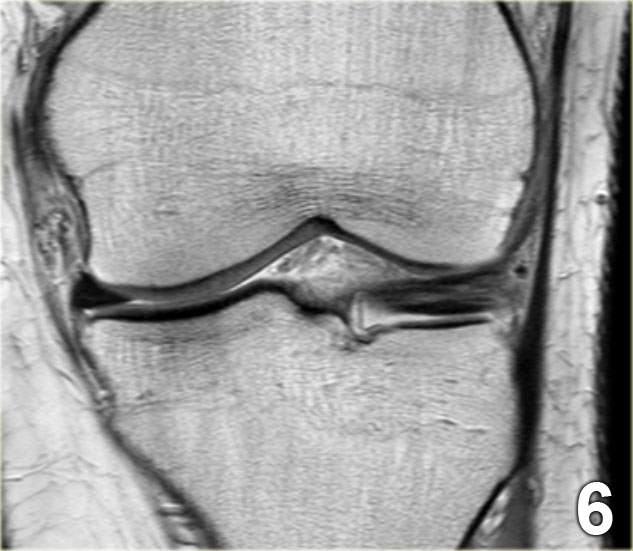

Rách kiểu quai xách là loại rách dọc theo chiều đứng có kèm di lệch.

Mảnh bờ trong bị di lệch có hình dạng giống như quai của một chiếc xô.

Phần ngoại vi còn lại của sụn chêm, phần lớn hơn, có hình dạng giống như thân chiếc xô.

Loại rách này chiếm khoảng 10% trong tổng số các trường hợp rách sụn chêm.

Dấu hiệu PCL đôi

Dấu hiệu dây chằng chéo sau (PCL) đôi là một dải giảm tín hiệu nằm song song và ở phía trước-dưới so với PCL trên ảnh MRI mặt phẳng đứng dọc.

Đây là dấu hiệu có độ đặc hiệu cao trong chẩn đoán rách sụn chêm kiểu quai xô (3).